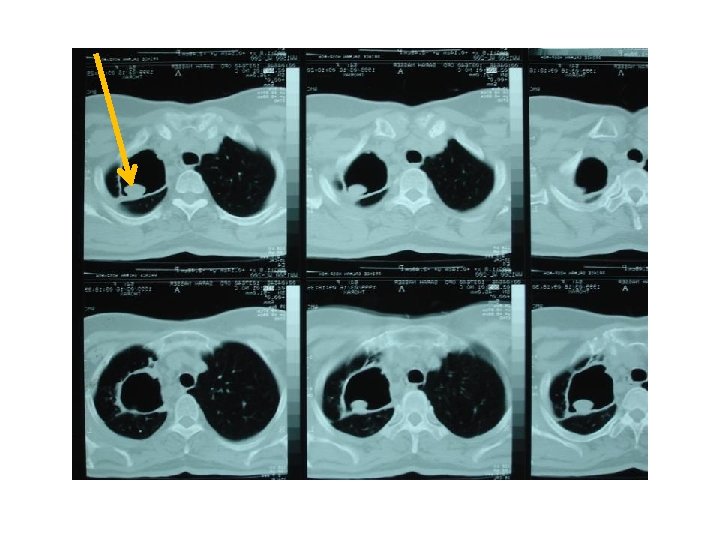

CT scan : infiltration , abcess formation , Lymph node

C. Tuberculosis * 30, 000 new cases occur annually in U. S. A § Cause ‒ Pulmonary ‒ Extra-pulmonary ( pleura , mediastinum ) § Investigation ‒ CXR ‒ CT scan. infiltration , abcess formation , Lymph node ‒ AFB sputum Culture. ( +ve ) Acid-fast bacillus smear and culture ‒ Bronchoalveolar lavage ‒ Mediastinoscopy (caseating granuloma)

§ Treatment ‒ Medical ‒ Surgical ü Failure of medical Rx ( Resist. 1 st , 2 nd , 3 rd Line of ttt) ü Destroyed lobe or lung ( left bronchus syndrome ) cuz can lead to ( inflammation , infection , abcess formation , septic state. . Pt needs to be admitted continueously due to chest infection or TB ! ü Pulmonary haemorrhage ü Persistent open cavity with + ve sputum ü Persistent broncho pulmonary fistula )